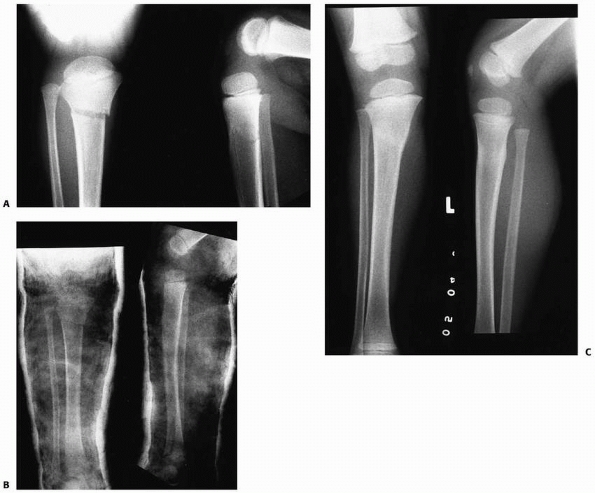

FIGURE 25-4 A.

Anteroposterior and lateral radiographs of the proximal tibial metaphyseal fracture with an intact fibula in a 3-year-old child. B. Anteroposterior and lateral radiograph in the initial long-leg cast demonstrate an acceptable alignment. C. Posttraumatic tibia valga is present 1 year after fracture union. (From Sharps CH, Cardea JA. Fractures of the shaft of the tibia and fibula. In: MacEwen GD, Kasser JR, Heinrich SD, eds. Pediatric Fractures: A Practical Approach to Assessment and Treatment. Baltimore: Williams & Wilkins, 1993:321, with permission.) |